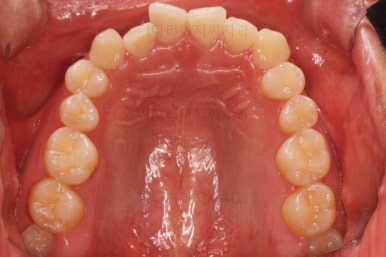

위아랫니가 모두 삐뚤어요.

특히 앞니가 삐뚤고 위아래 앞니가 고르게 덮여있는게 아니라 뒤죽박죽 엉켜있어서 치아의 마모도 굉장히 많이 되어있는 상태였어요.

이번 환자분은 치아가 삐뚤어 있는 양 + 돌출감을 고려했을 때 비발치로 가능할 것이라고 판단이 되었어요.

굳이 입이 들어가길 원하시거나 혹은 교정 중에 튀어나온다고 느끼신다면 사랑니 자리를 확보해 통째로 뒤로 살짝 밀언허는 방법도 있기 때문에 비발치 교정을 추천드렸어요.